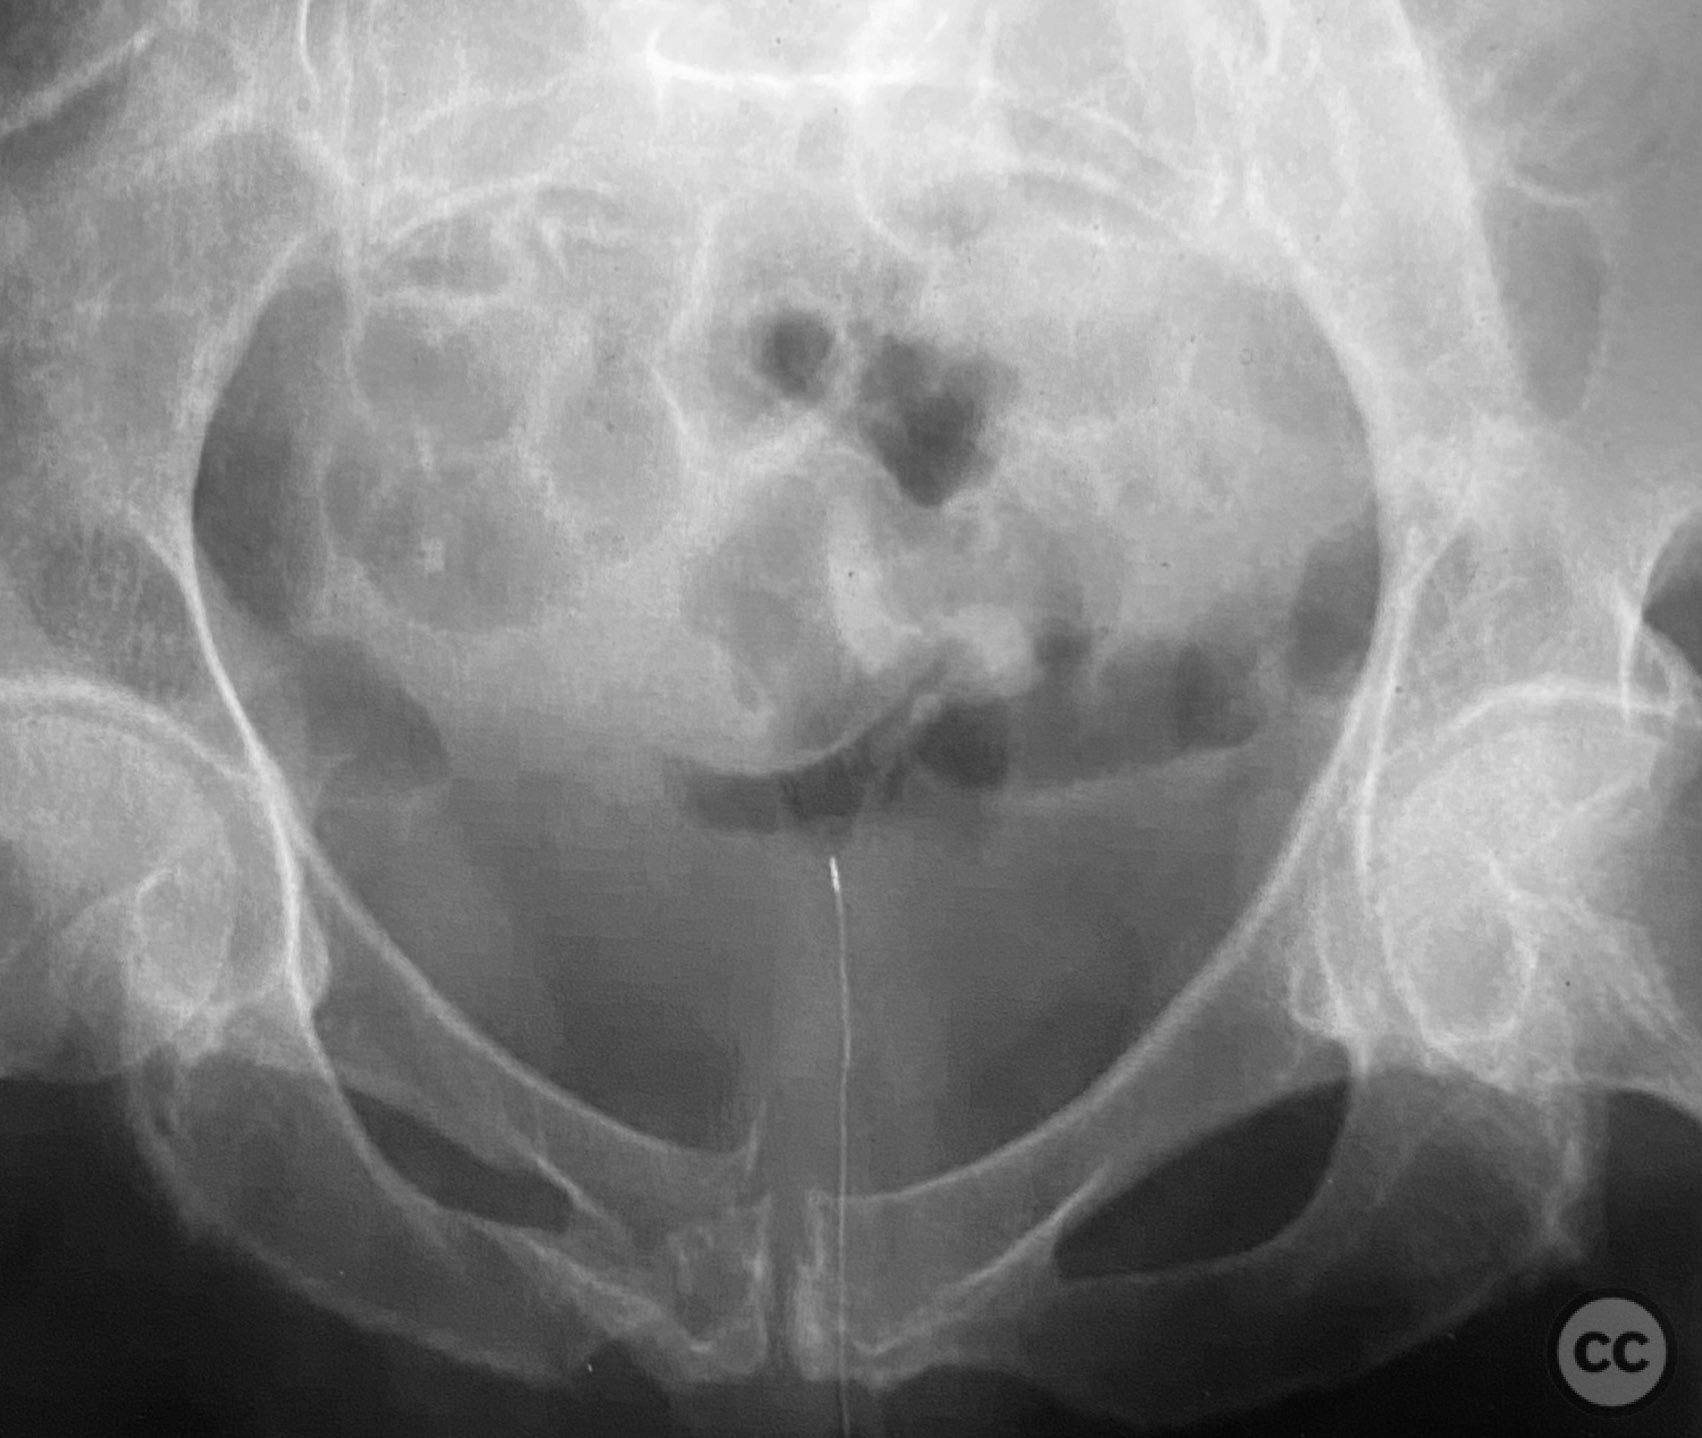

Clinical and radiological findings:  Adult patient presenting with severe pelvic pain, unable to sit or transfer to a chair. Clinical examination under anesthesia demonstrated pelvic instability with “rebound reduction” upon minimal iliac crest compression. Imaging revealed an unstable superior pubic ramus fracture with challenging anterior pelvic bone anatomy and dense cortical bone at the anterior acetabular wall.

Planning remarks:  Planned trans-symphyseal fixation of the superior pubic ramus fracture using a 4.5mm cortical screw, with preoperative intent to maximize implant purchase in stable bone regions. Surgical approach selected to facilitate direct access to the superior pubic ramus and symphysis pubis.

Intraoperatively, a 3.5mm drill was used through a protective sleeve to initiate the screw pathway across the superior pubic ramus. Due to poor bone quality, a 2.5mm drill was subsequently employed; however, resistance was encountered as the drill tip engaged the dense cortical apex of the anterior acetabular wall. The drill became lodged in this region. To avoid drill breakage, manual extraction using pliers was considered; however, the surgeon elected to carefully deflect and advance the drill manually, successfully completing the pathway. Screw length was measured directly from the embedded drill tip. A 4.5mm cortical screw was then inserted trans-symphyseally along the prepared medullary canal, achieving stabilization of the unstable ramus fracture. Postoperative CT confirmed appropriate screw trajectory and demonstrated the dense cortical bone at the anterior acetabular wall where the drill tip had engaged.